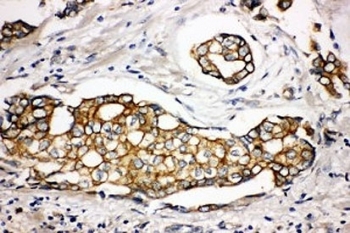

IHC staining of FFPE human breast cancer tissue with SPTLC1 antibody. HIER: boil tissue sections in pH8 EDTA for 20 min and allow to cool before testing.

Immunohistochemistry (FFPE) : 2-5ug/ml